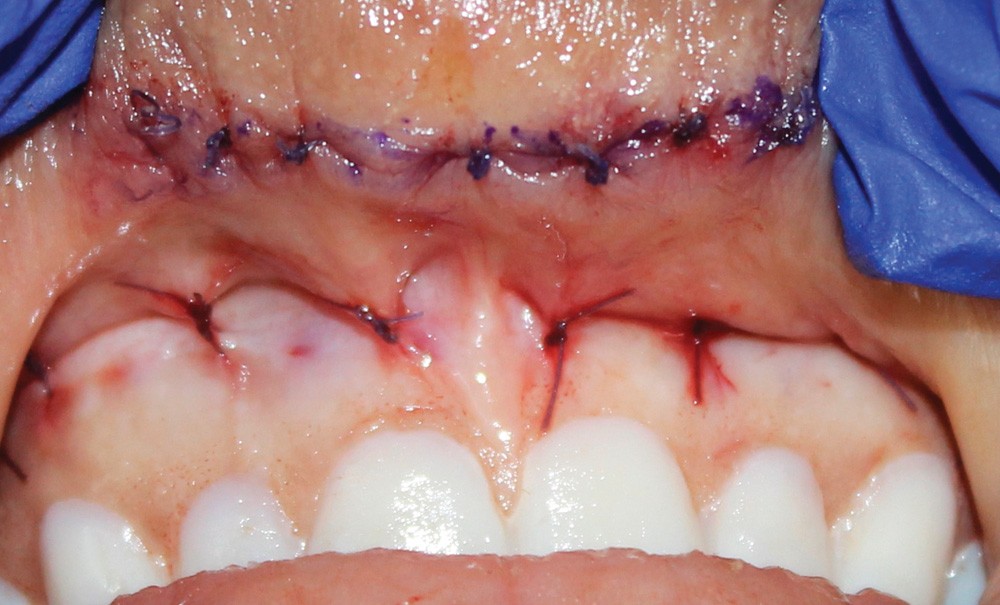

- Le traitement de repositionnement ou de stabilisation de la lèvre (qui est indiqué surtout en cas hypermobilité labiale) (fig. 2 et 3) [11,12].